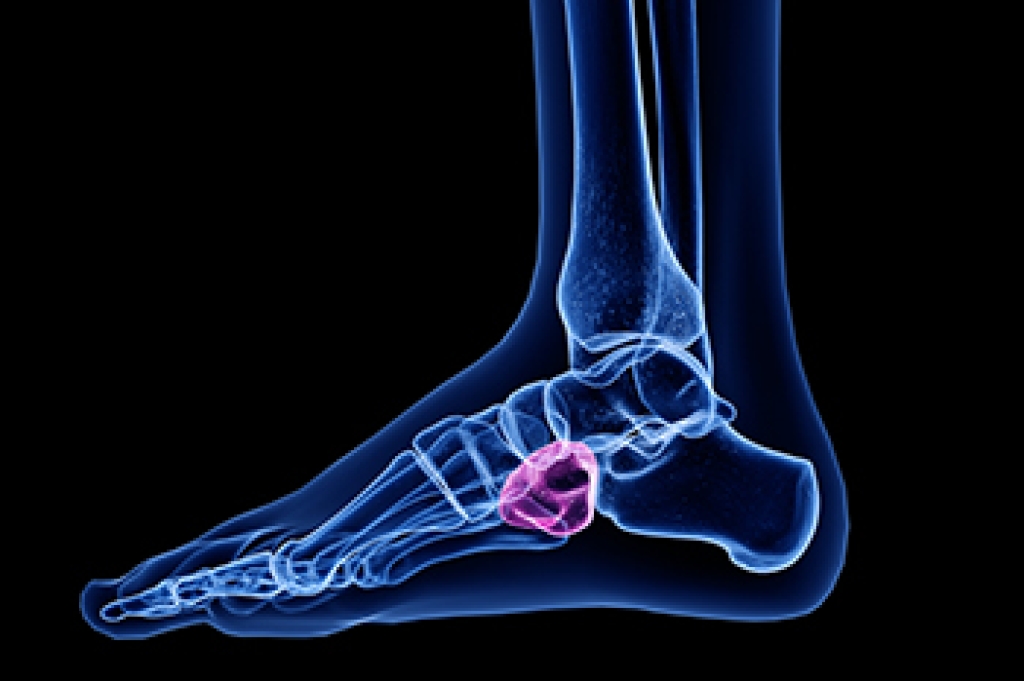

Hammertoe is a deformity where one of the smaller toes becomes bent at the middle joint, causing the toe to arch upward instead of lying flat. This misalignment often affects the second, third, or fourth toe and can lead to discomfort, especially when wearing shoes with a narrow or low toe box. Common symptoms of hammertoe can include corns, open sores, and pain in the ball of the foot. Various factors can contribute to a hammertoe, including having an unusually long toe, muscle weakness, or rheumatoid arthritis. Injuries, pressure from bunions, and wearing improperly fitting shoes can also result in hammertoe formation. A podiatrist can diagnose hammertoe through a physical examination of the foot and recommend treatment options such as wearing wider shoes, using toe pads, or performing specific foot exercises. In more severe cases, surgery may be required to correct the deformity. If you have a painful hammertoe, it is suggested that you schedule an appointment with a podiatrist for an exam and treatment.

Hammertoe is a foot deformity that affects the joints of the second, third, fourth, or fifth toes of your feet. It is a painful foot condition in which these toes curl and arch up, which can often lead to pain when wearing footwear.

Arthritis – Because arthritis affects the joints in your toes, further deformities stemming from arthritis can occur